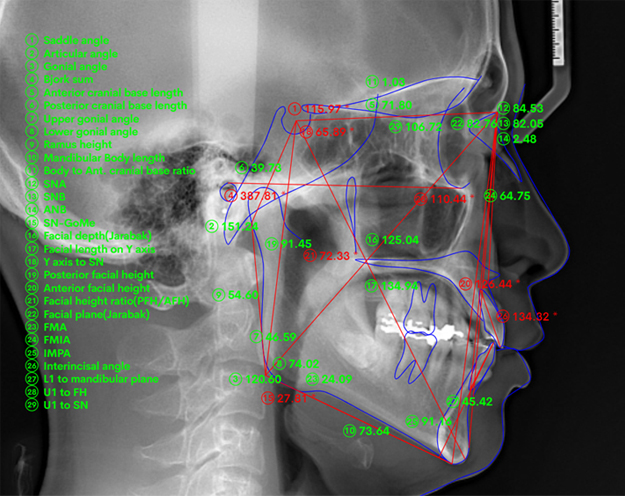

• 02 Skeletal Analysis

80가지 정밀 악골관계 분석

환자의 부정교합의 원인을 정밀하게 분석하고

치료방향을 제시하는 서동휘 대표원장만의 분석법입니다.